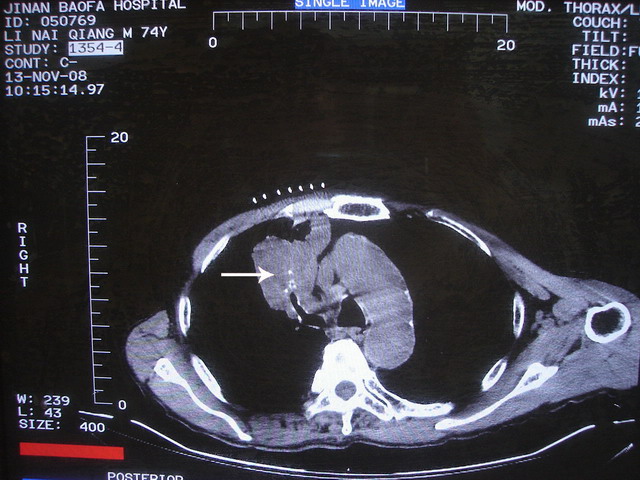

缓释库疗法治疗19天后

李XX,74岁,山东人,住院号:001313,08年10月因阵发性干咳伴左胸部疼痛,被省级医院诊为右肺鳞癌并左肺、肺门、纵隔淋巴结转移。08年10月24日住我院,10月25日CT示右肺7.6cmX6.1cm肿块,上叶前段支气管阻塞。行缓释库疗法、活化化疗,19天后11月13日CT显示肿瘤组织部分坏死吸收,缩小1/4,治疗效果明显,现病人自我感觉很好,继续观察治疗中。